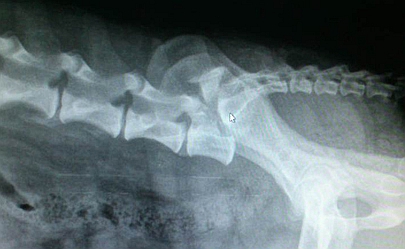

Zwichnięcie kręgosłupa na poziomie trzonu kręgów L7 - S1 jest stosunkowo częstym następstwem wypadków drogowych u psów. Dodatkowym obrażeniem towarzyszącym zwichnięciu na opisywanym poziomie jest złamanie z przemieszczeniem trzonu kręgu L7, złamanie z przemieszczeniem wyrostka stawowego (przykład w zamieszczonych radiogramach). Leczeniem zwichnięcie kręgosłupa na poziomie L7-S1 jest osteosynteza z użyciem wkrętów ortopedycznych i gwoździa śródszpikowego. Należy pamiętać, że w każdym przypadku konieczne jest badanie neurologiczne oraz radiograficzne.